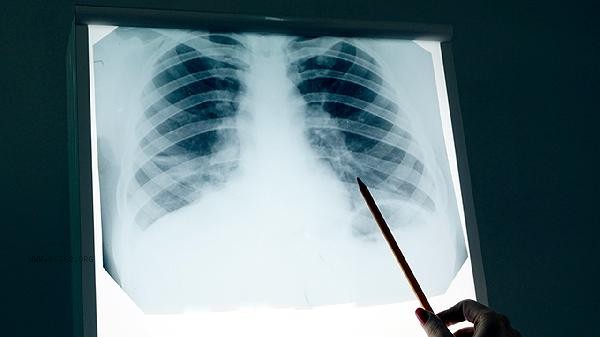

Pulmonary artery small branch embolism is usually not an early manifestation of lung cancer, and the two belong to different pathological mechanisms. Pulmonary embolism is mainly caused by thrombus obstruction, while early lung cancer often presents with local symptoms such as cough and phlegm blood. Pulmonary embolism may be induced by venous thromboembolism, hypercoagulable state of blood, endothelial injury, long-term bed rest, tumor related factors, etc. Typical symptoms include sudden dyspnea, chest pain, and hemoptysis.